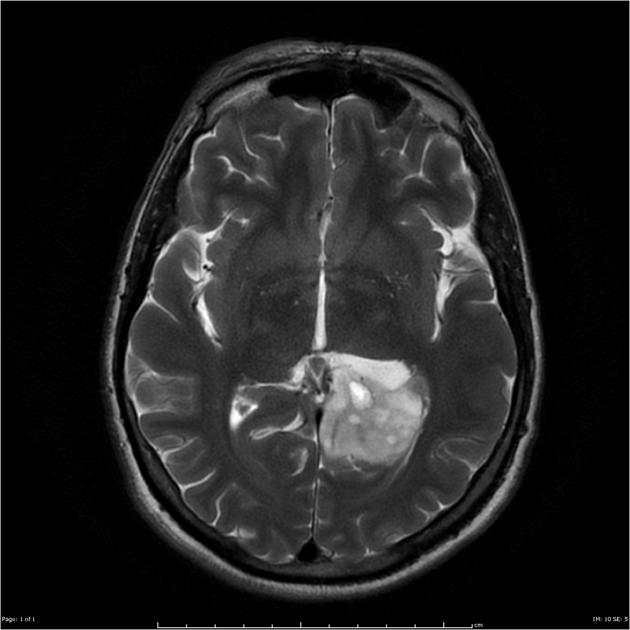

After a careful H&P with attention to neurologic symptoms, time of onset and rate of increase, imaging is critical to localization and diagnosis. Surgery, including a complete debulking if possible is the first line treatment, and sets the stage for the next step. Imaging is predominantly MRI based, with T1 ±gad, T2, FLAIR, diffusion weighted, and gradient echo sequences to identify and localize the extent of disease. Surgery is used to debulk the tumor completely if possible, and if not to obtain tissue for diagnosis.

Imaging

GBM T2

Radiotherapy General Fields

The treatment fields for HGG in pediatrics, similar to adults is the imaging enhanced region plus a margin. The initial GTV is the MRI T2 abnormality (edema). The initial CTV = GTV + 1.5 cm, corrected for anatomical barriers. The usual dose to this volume is 50.4 - 54 Gy at 1.8 Gy/fraction. The second GTV (boost GTV) is the T1+gadolinium enhancement. The second CTV=GTV+1 cm. This is then carried to 59.4 Gy.

• initial GTV = T2 or FLAIR mri image

• The CTV is the T2 GTV+1.5 cm margin, with corrections for anatomical barriers (⇒ 50-54 Gy)

• The final GTV = T1+ gad image

• The final CTV = GTV (final) + 1 cm margin (⇒ to 59.4 Gy)